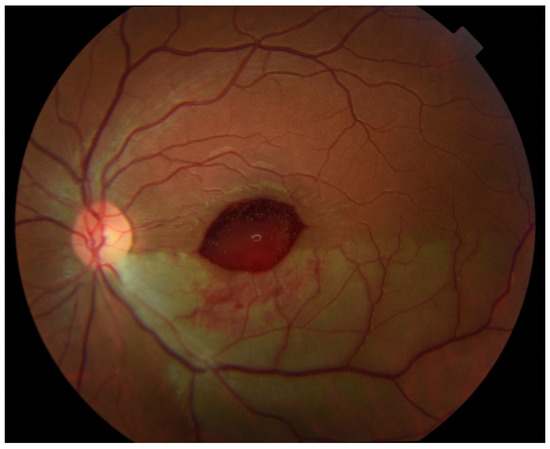

At 7 weeks after the onset of the BRAO, visual acuity in the left eye had dropped to 20/50 and color fundus photos revealed a yellowish discoloration over the fovea (Figure 4), consistent with dehemoglobinized blood. Humphrey visual fields revealed a stable defect. SD-OCT (Spectralis; Heidelberg Engineering, Heidelberg, Germany) showed inner retina hyperreflective material beneath the internal limiting membrane (ILM) consistent with resolving hemorrhage, along with expected thinning and loss of inner retinal layers in the distribution of the BRAO (Figure 5).

Figure 5. Horizontal (A) and vertical (B) spectral domain OCT B-scans show hyperreflective material deep to the attachment between the posterior hyaloid and the internal limiting membrane (ILM) and filling the foveal depression suggestive of residual hemorrhage. Note the thinning of the inner retinal layers inferiorly from recent branch retinal artery occlusion (arrowhead).